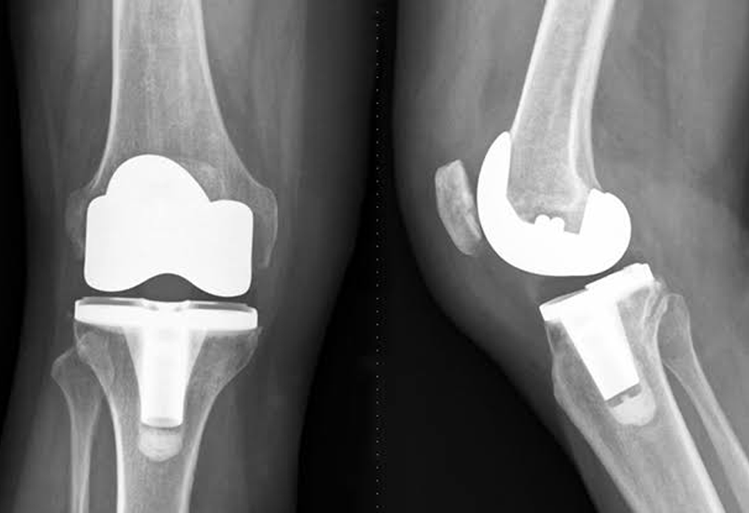

Total Knee Replacement

Knee replacement, also called knee arthroplasty or total knee replacement, is a surgical procedure to resurface a knee damaged by arthritis. Metal and plastic parts are used to cap the ends of the bones that form the knee joint, along with the kneecap. This surgery may be considered for someone who has severe arthritis or a severe knee injury.